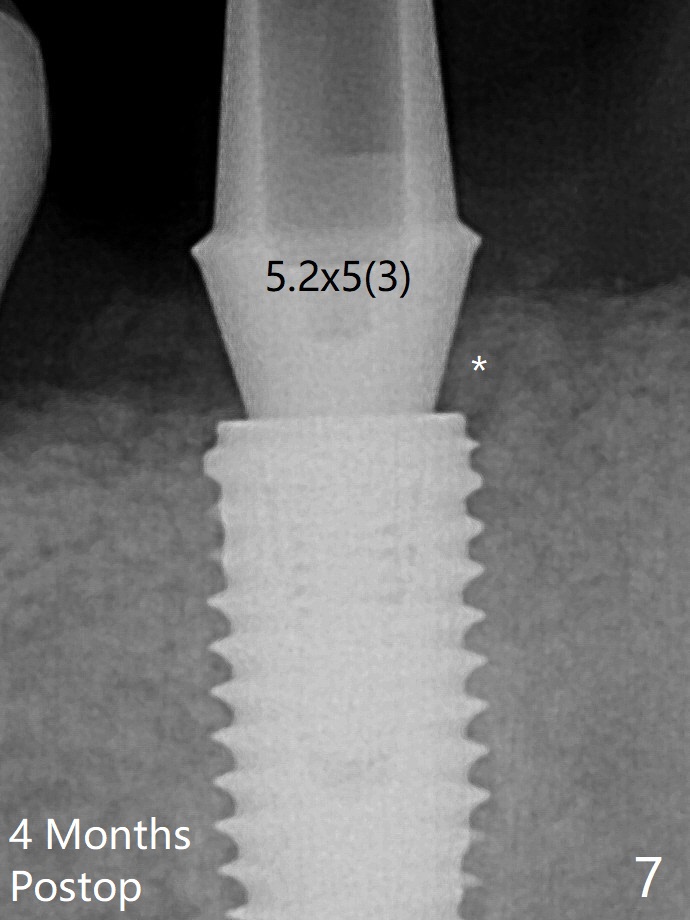

小一号基台仿佛完全就位(图八(咬翼片);图七(根尖片,可能失真)),但是临床上没有听到清脆声音(可能软硬组织阻挡)。随着时间推移,远中牙槽嵴吸收,当松动基台螺丝再次拧紧,可能会真正完全就位,必须拍摄完美咬翼片证实。这种植体芯(body, not threads)特别厚内部结构看不清楚。